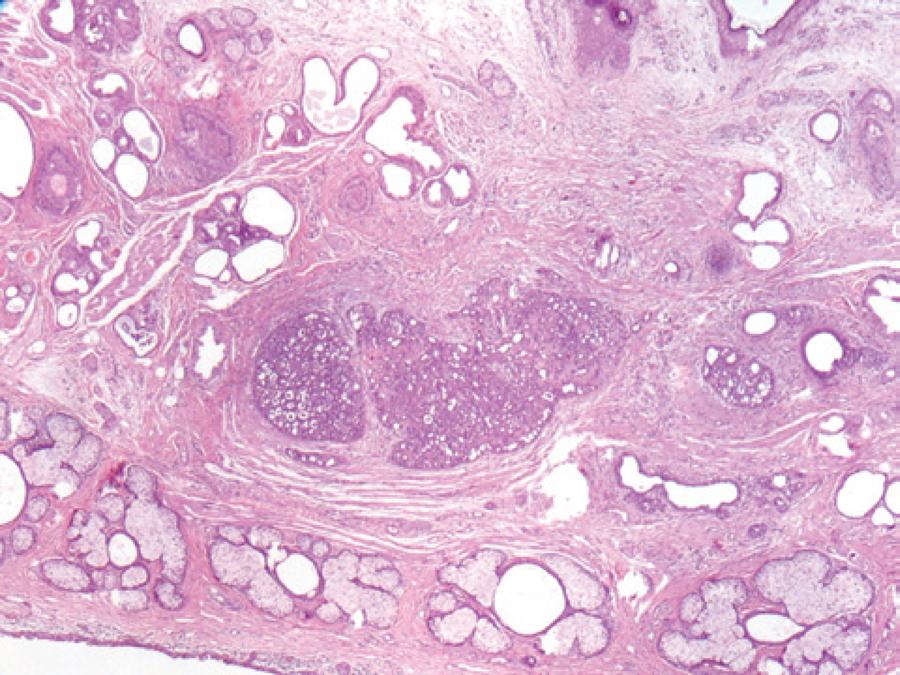

A 52-year-old male was admitted to the Oculoplasty Unit at the Antalya Research and Training Hospital complaining of a mass lesion in the right lower eyelid. The flesh-colored mass lesion measured 3 × 4 mm, was not causing significant irregularity in the eyelashes, and had grown slowly over approximately 4 years (Figure 1). Incisional biopsy was performed with a provisional diagnosis of suspected chalazion or tumor. Microscopic examination revealed a poorly circumscribed dermal tumor composed of basaloid cells with a glandular, cystic, and cribriform arrangement embedded in a loose fibrous stroma, in which the cystic spaces contained abundant alcian blue-positive (pH 2.5) mucin (Figure 2).

Figure 2 A poorly circumscribed dermal tumor showing a glandular and cribriform pattern in the dermis (H&E staining, magnification ×40).